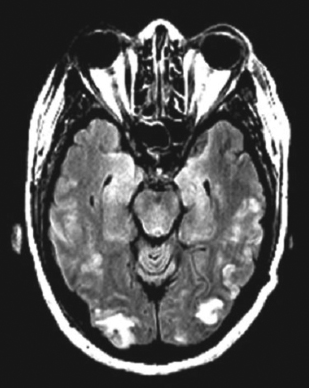

Her white blood cell count is 14,800/μL with a normal differential. Her red blood cell and platelet counts are normal. Serum chemistry, liver function, and coagulation test results are normal. Urinalysis reveals a protein level of higher than 500 mg/dL. A T2-flair image from an MRI scan is shown here.

PRES is a distinct radiologic pattern of vasogenic edema in the setting of neurotoxicity that is strongly associated with eclampsia. The syndrome is distinguished by its focal, symmetric distribution in watershed areas of the parietal and occipital areas of the brain. Contrary to the name, PRES can affect frontal, brainstem, or cerebellar zones as well. Symptoms associated with PRES include headaches, vision changes, focal neurologic signs, alterations in mental status, and seizures. PRES is not unique to eclampsia and is observed in a number of other conditions (Table). PRES is thought to be fully reversible with management of the underlying disorder.4,5